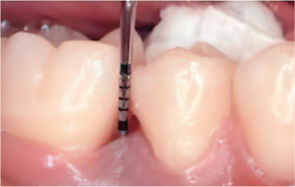

Before & After